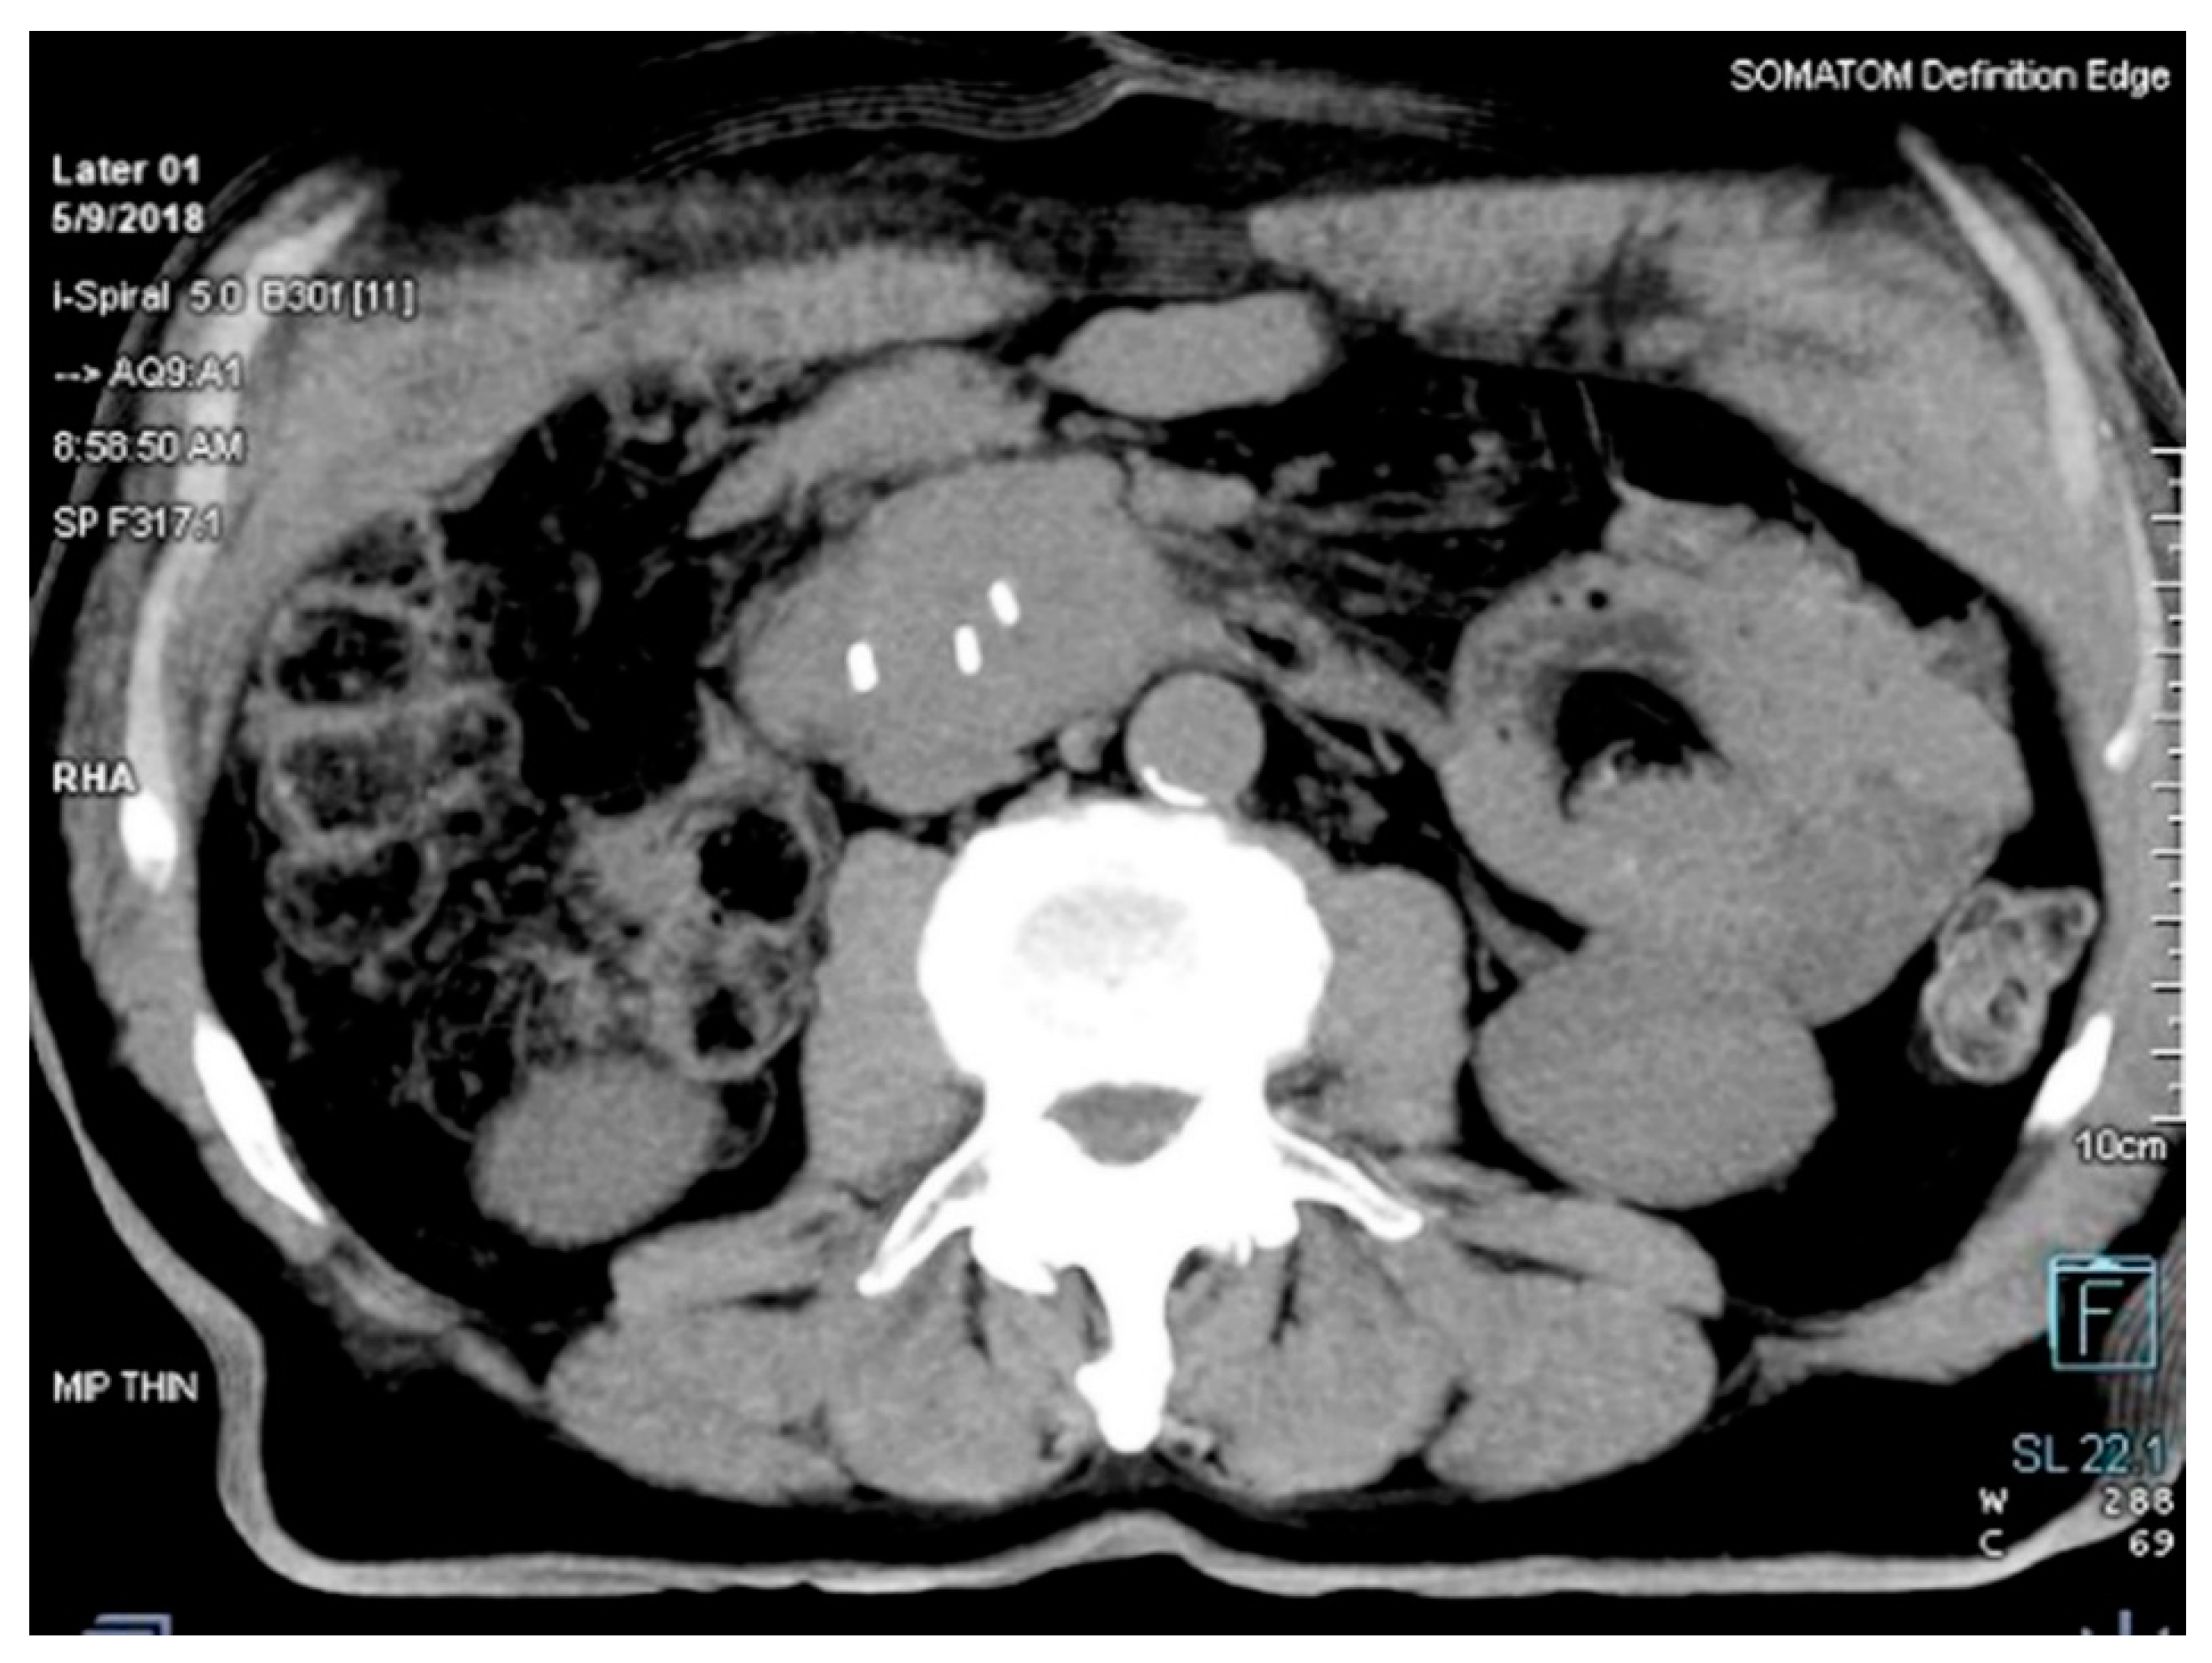

The distance between transponders in the lesion was minimum 1 cm, and maximum 7 cm, according to the manufacturer’s manual, to provide accurate motion tracking (

Figure 2).